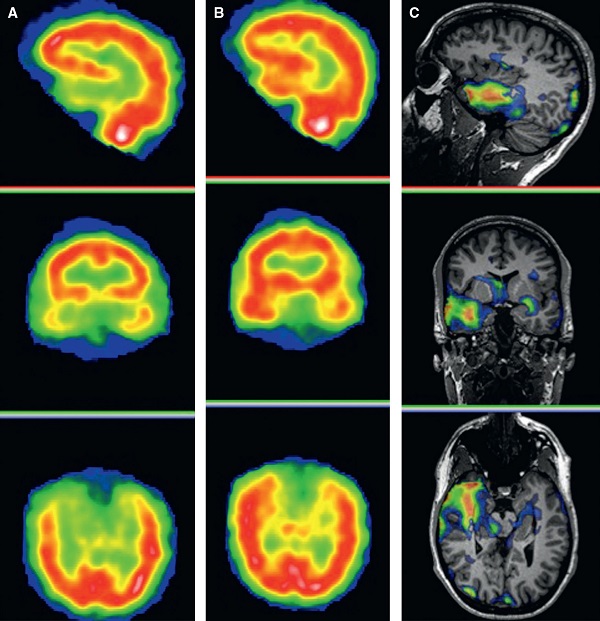

تشخيص تومورهاي مغزي در تصاوير MRI يا تعيين نواحي فعال مغز حين انجام کارهاي خاص.